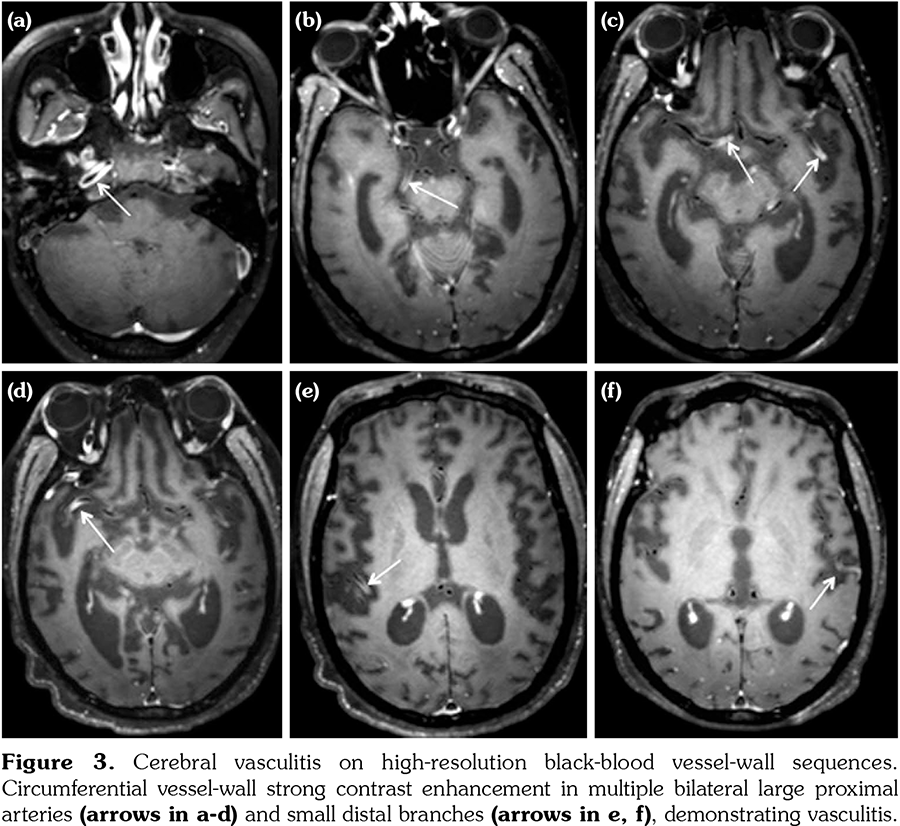

Initial brain MRI, using a standard protocol, was normal (Figures 1a and 2a). Due to rapid deterioration of the neurological status, a follow- up MRI was performed three weeks later (Figures 1b and 2b), including gadolinium administration and angiographic sequences. A mild periventricular nonspecific leukoencephalopathy and an incipient dilation of the supratentorial ventricles were observed. No abnormal contrast- enhancement was present. MRI angiography and venography showed permeability of the vessels. The patient continued to deteriorate, in a span of several weeks, despite initiating high-dose intravenous methylprednisolone. The clinical suspicion of vasculitis was raised and a third MRI was performed, at 3.5 months from the onset, with a specific protocol including vessel-wall three-dimensional (3D)-high-resolution pre- and post-contrast black-blood sequences. This MRI showed severe progression of the leukoencephalopathy, and associated atrophy with marked dilation of the ventricles and the subarachnoid spaces (Figures 1c and 2c). High-resolution vessel-wall sequences showed multiple arterial segments with concentric contrast enhancement of the wall, of proximal and distal distribution (Figure 3), compatible with vasculitis. A treatment with high-dose intravenous cyclophosphamide was started. Clinical follow- up revealed a progressive improvement of the drowsiness with eventually stabilized neurological status, but the cognitive deficit was already extremely impaired. The fourth MRI exam, at seven months from the clinical onset, showed even more severe atrophy (Figures 1d and 2d). A comparative of the hippocampal formation, crucial for the memory circuit, showed normal features on the first MRI (Figure 2e) and marked “knife blade” atrophy on the last study (Figure 2f). Concomitant diseases, including cerebrovascular and cardiovascular events, were ruled out.

Neuropsychiatric SLE remains a major cause of morbidity in patients with SLE, despite all recent diagnostic and therapeutic advances. The most frequent MRI abnormalities in NPSLE are white matter lesions and brain atrophy, although the reported frequencies vary widely, probably reflecting the heterogeneity of the studied population.[7,8] The presence of cortical atrophy was reported at a mean age of 42.5 years in NPSLE.[7] Less frequently, NPSLE patients could present inflammatory lesions on MRI, which usually disappear after aggressive corticosteroid or immunosuppressive treatment. They were reported in 6.5% of patients, and were correlated with low complement levels, supporting an immune-mediated pathogenesis of NPSLE.[9] This pattern has been related to primary cerebral vasculitis, which is however considered to be uncommon in SLE.[2,7,10] Post-mortem histopathological studies reported cerebral vasculitis in less than 10% of NPSLE patients.[9,11] Imaging findings of vasculitis in NPSLE were rarely described, when angiography exams revealed focal beadings and circumferential stenosis of arteries.[12-14] On the other hand, a normal angiography cannot rule out vasculitis, and angiography exams are usually normal if small vessels are involved.[11,14] Despite a low risk of complications, a brain biopsy is usually avoided, lacking of high sensitivity due to the sampling error with high false-negative rates. Therefore, no “gold standard” diagnostic test is accepted to date for the diagnosis of cerebral vasculitis.[13,14] Recently, specific vessel-wall sequences emerged. This type of imaging requires a high-field MRI (3T), and the availability of high-resolution (around 0.5 mm isotropic) 3D-black-blood sequences, acquired pre- and post-gadolinium administration.[14-17] Recent technological advances and guidelines were developed to optimize these sequences and to reduce the acquisition time on the one side,[15] and to provide expert consensus recommendations for their implementation in the current clinical practice on the other side.[16,17] This vessel-wall imaging is increasingly used in other pathologies as aneurysms, dissection and strokes. Prospective comparative studies evaluating the feasibility of 3D-black-blood pre- and post-contrast sequences demonstrated that this technique accurately allows the diagnosis of vasculitis, and the intensity of contrast enhancement of the wall correlated with the mural inflammation.[18] In the last year, several publications including these sequences reported vasculitis of different etiologies as varicella- zoster,[19] Sjögren syndrome,[20] or primary vasculitis of the central nervous system.[21] A recent study analyzed the vessel-wall imaging at 3 Tesla MRI in a cohort of SLE patients, and compared the data with a group of healthy controls.[22] They demonstrated different types of vessel-wall focal lesions, more frequent in SLE group, particularly of the first segments of the middle cerebral artery. Moreover, vessel-wall lesions were associated with brain infarctions. Another recent report applied MRI angiography, vessel-wall imaging and transcranial Doppler and described multifocal stenosis of the intracranial arteries in two patients with SLE who presented non-aneurysmal subarachnoid hemorrhage.[23] They concluded that the hemorrhage was due to vasculitis or to reversible cerebral vasoconstriction syndrome and that vessel-wall imaging is an important tool for the diagnosis.